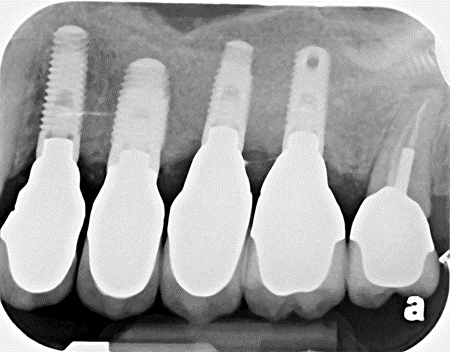

When there’s no available bone beneath the sinus floor (Fig. 1), we perform a full (external) sinus lift. We elevate the Schneiderian membrane and pack in bone graft material (Fig. 2). After 6-9 months, the new bone allows implant placement (Fig. 3). Four months later, those implants are restored with abutments and crowns (Fig. 4).

Fig. 3: Implants with Final Abutments and Crowns in New Bone